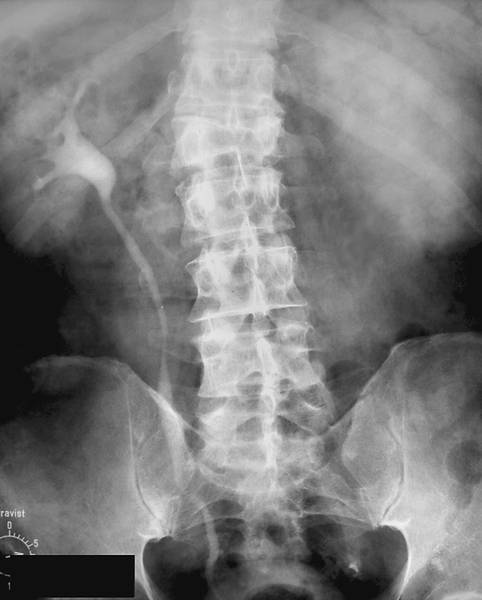

ОБЗОРНЫЙ СНИМОК

Любое рентгенологическое исследование в урологии необходимо начинать с обзорного снимка мочевой системы (рис.).

Обзорный снимок органов мочевой системы.

Интерпретацию обзорного снимка начинают с рассмотрения костного скелета: поясничных и нижних грудных позвонков, рёбер, тазовых костей. Иногда на нём удаётся увидеть тени почек, которые расположены слева между телом XII грудного и II поясничным позвонком, справа — между верхним краем I поясничного позвонка до тела III поясничного позвонка. Следует обращать внимание на их форму, величину и контуры, изменение которых позволяет заподозрить патологический процесс в почках. В норме тень правой почки несколько короче и шире левой. Это связано с разным углом наклона вертикальной оси почек по отношению к позвоночнику. Нужно обратить внимание на степень плотности тени, как по всей её площади, так и в отдельных сегментах. Далее обращают внимание на тень поясничных мышц (m. psoas). В норме она имеет вид усечённой пирамиды, вершина которой расположена на уровне тела XII грудного позвонка. Изменение или исчезновение контуров этой мышцы на одной из сторон наблюдают при воспалительных или опухолевых процессах в забрюшинном пространстве. Отсутствие тени поясничных мышц при травме почки свидетельствует о наличии урогематомы в забрюшинном пространстве.

Мочеточники в норме на обзорном снимке не видны. Иногда, если мочевой пузырь наполнен насыщенной мочой, заметна его тень. В норме на обзорном снимке он имеет форму эллипса.

После оценки естественных структур обращают внимание на наличие добавочных теней. Они различаются по форме, величине, контрастности, однородности. Часто на рентгенограмме видны просветления, обусловленные кишечными газами.